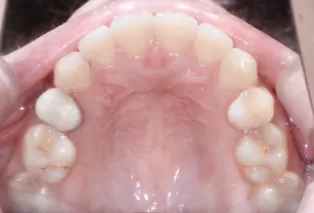

Photos intra-orales